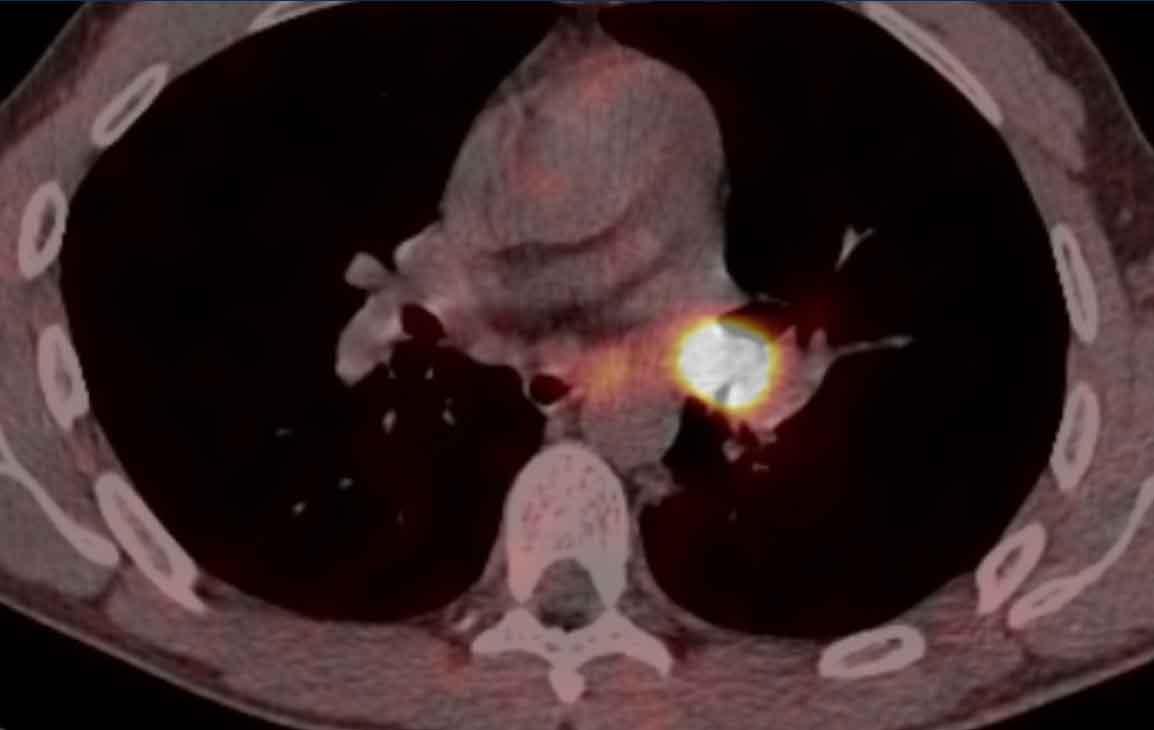

Hình ảnh

PET-CT cho thấy hấp thu cao tương ứng với tổn thương dạng nốt nhỏ ở khí quản đoạn gần ở nữ giới 52 tuổi có tiền sử ung thư đại trực tràng.

Giải phẫu bệnh: Di căn của ung thư đại trực tràng.